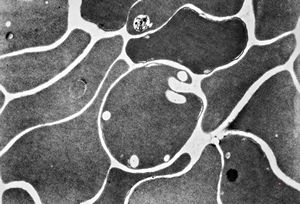

F,68y. | spleen - undefined myelinoid inclusions - clin. susp. leukemia

F,68y. | spleen - myelinoid inclusions - clin. susp. leukemia